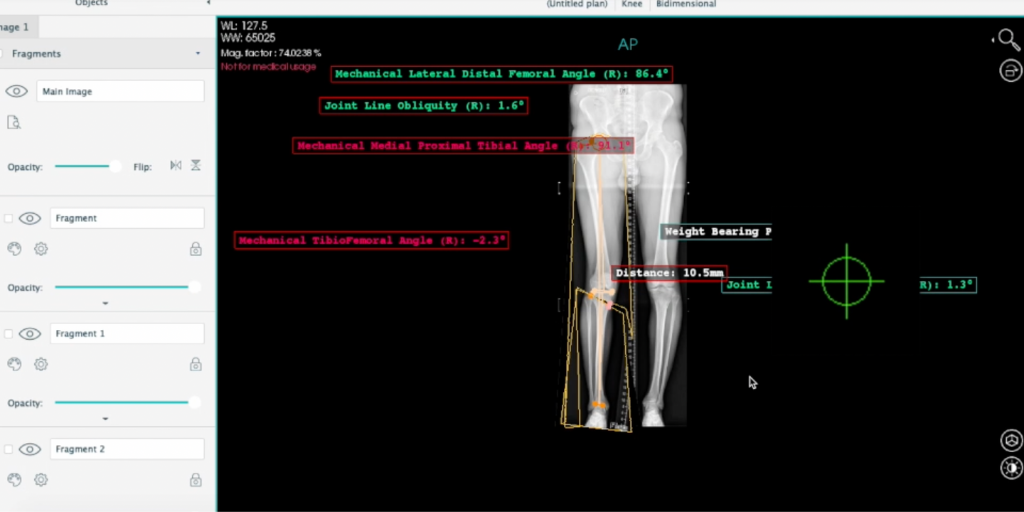

The study detailed the inclusion of anatomical landmarks in PeekMed, which allows accurate and reproducible angular value measurements. The system’s automatic knee osteotomy planning feature analyzes both the tibial and femoral metaphyseal deformities, providing recommendations for the optimal procedure and degree of openness to achieve the desired mechanical axis without inducing excessive joint line obliquity in HTO cases.